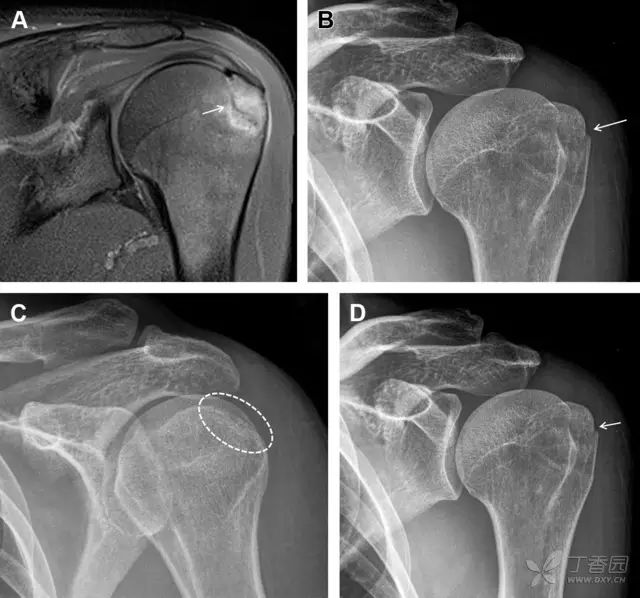

图 1 大结节骨折。(A)脂肪抑制序列斜冠状位 MRI,显示肱骨大结节线性骨折无移位(箭头)与周围骨水肿;(B)外旋位前后位(AP)片,证实大结节骨折(箭头),典型的骨折愈合过程中的骨吸收表现;(C、D)初诊时内旋位、外旋位前后位片,初诊时漏诊,仔细回顾影像,内旋伞下可见双密度影(椭圆),骨皮质中断(箭头)